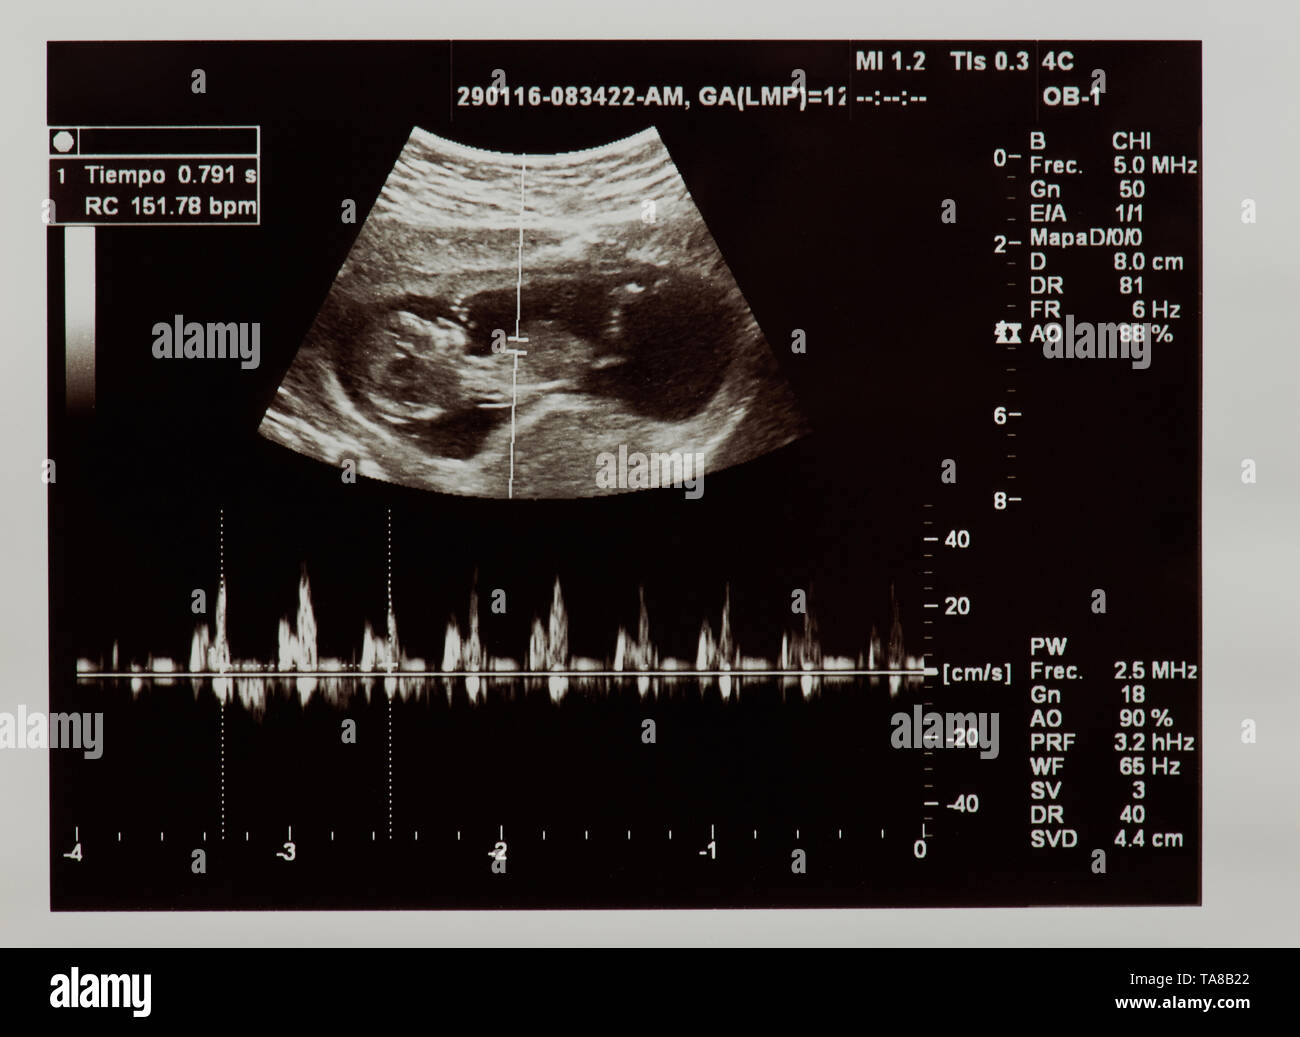

Scansione a ultrasuoni del futuro bambino con il battito cardiaco parametri Foto Stockhttps://www.alamy.it/image-license-details/?v=1https://www.alamy.it/scansione-a-ultrasuoni-del-futuro-bambino-con-il-battito-cardiaco-parametri-image247276010.html

Scansione a ultrasuoni del futuro bambino con il battito cardiaco parametri Foto Stockhttps://www.alamy.it/image-license-details/?v=1https://www.alamy.it/scansione-a-ultrasuoni-del-futuro-bambino-con-il-battito-cardiaco-parametri-image247276010.htmlRFTA8B22–Scansione a ultrasuoni del futuro bambino con il battito cardiaco parametri